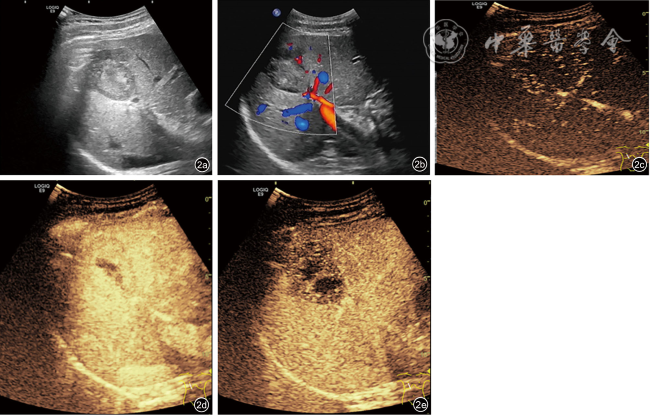

患者男性,42岁,右下腹酸胀疼痛3个月,无发热、寒战、周身黄染等其他症状,无肝炎病史。深圳市人民医院门诊CT检查发现肝右叶一类圆形低密度影,边界欠清楚,大小约4.5 cm×4.2 cm,增强扫描呈填充式强化,内壁欠光整,病灶内见小片状无增强区,动脉期病变周围见异常灌注(图1)。CT提示:肝右叶占位,考虑肝脓肿可能性大,肿瘤性病变待排查。实验室检查:直接胆红素浓度为8.5 μmol/L,总胆红素浓度为30.7 μmol/L,丙氨酸氨基转移酶40.1 U/L,碱性磷酸酶125 U/L,其余指标均在正常范围内。中性粒细胞比值、中性粒细胞绝对值在正常范围内,肿瘤标志物癌胚抗原、甲胎蛋白、糖类抗原199均阴性。入院行抗感染治疗1周后复查超声:肝右前、后叶交界处可见一大小约4.9 cm×4.6 cm实质性团块,形状欠规则,内部为不均质低回声,边界尚清楚,无声晕,彩色多普勒血流成像见团块周边较丰富血流信号,内部见少量血流信号。超声造影:经肘静脉团注造影剂2.4 ml,14 s肿块周边实质呈快速不均匀增强;24 s达峰值,中央可见无增强区,范围2.6 cm×1.5 cm;于门脉期早于周边实质开始消退,延迟期进一步消退(图2);结合超声造影提示:考虑肝细胞癌可能,肝脓肿待排查。进一步行磁共振造影检查:肝右叶见大小4.9 cm×3.5 cm类圆形长T1稍长T2信号影,弥散明显受限,中央见小片状长T1短T2区域,中央区域弥散未见受限,增强扫描病灶各期呈环形强化,中央未见明显强化,肝胆期未见明显造影剂摄取(图3),诊断:考虑肝脓肿,纤维板层样肝癌待排查。此后1周内多次复查腹部超声,均提示肝占位病变无明显变化,临床排除肝脓肿可能,考虑肝细胞癌可能性大。遂行机器人辅助腔镜下肝S8段切除术。常规病理:肿瘤大小4.0 cm×4.0 cm×3.5 cm,与周围肝组织界限尚清楚,在大量淋巴细胞、浆细胞、组织细胞及多核巨细胞的背景下,见梭形滤泡树突样或纤维母细胞样细胞呈条束状分布,核空泡状、核仁明显,可见多灶性坏死;免疫组织化学检测结果显示肿瘤细胞CD21(+)、CD23(+)、CD35(+)、SSTR2(+)、SMA(-)、CD3(-)、CD20(-)、CD138(浆细胞+)、Ki-67(20%+)、IgG4/IgG(<40%);原位杂交结果:EB病毒(Epstein-Barr virus,EBV)壳抗原IgA抗体阳性[EBV脱核RNA(Epstein-Barr virus enucleated RNA,EBER)+]。最终病理诊断为EBV阳性炎性滤泡树突细胞肉瘤(EBV+ inflammatory follicular dentritic cell sarcoma,EBV+IFDCS)。术后未进行放化疗,随访16个月未见肿瘤复发及转移。

图1 肝病灶增强CT呈填充式强化,内壁欠光整,可见小片状无增强区。图a为动脉期,图b为门脉期,图c为延迟期